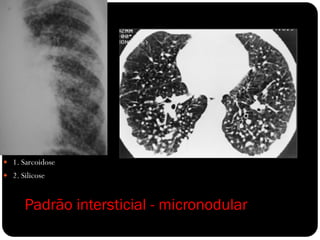

Padrão intersticial - micronodular

 1. Sarcoidose

 2. Silicose

Padrão intersticial -micronodular  1. Sarcoidose  2. Silicose